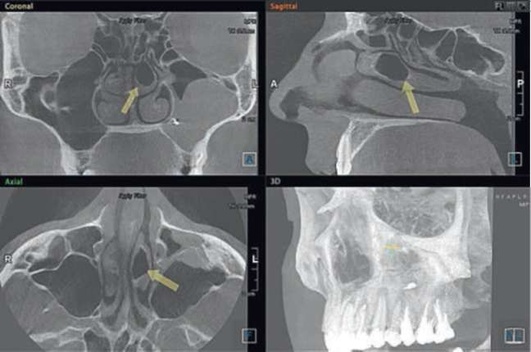

Адекватное хирургическое вмешательство и послеоперационное лечение способствуют выздоровлению. В некоторых случаях возможно самопроизвольное закрытие перфорации. Врачебная ошибка при обнаружении перфорации во время удаления зуба или вовремя нераспознанная перфорация могут привести к развитию острого перфоративного синусита. Пациенты нередко обращаются спустя несколько дней после удаления зуба с жалобами на выделения из лунки, попадание жидкости из полости рта в нос и воздуха из полости носа в рот. У львиной доли пациентов с перфорацией верхнечелюстной пазухи на основании КЛКТ были зарегистрированы деструктивные процессы в области нижней стенки ВС. Важным диагностическим этапом является проведение радиологического исследования, но вместе с тем следует указать, что проведение панорамной радиографии челюстей, черепа в аксиальной и других проекциях, зонограмм и радиологических исследований с применением контрастирующих средств на современном этапе не обоснованно в связи с низкой информативностью данных исследований. Эффекты суммации, нередко низкое качество получаемого изображения, плоскостные искажения не позволяют врачу проводить диагностику прецизионно, а учитывая уровень лучевой нагрузки, получаемый пациентом на рентгенологических аппаратах старых образцов, становится очевидно, что КЛКТ можно назвать «золотым стандартом» обследования пациентов с патологиями придаточных пазух носа (рис. 5.84, 5.85).

image

Рис. 5.84. Компьютерная томограмма до начала терапии острого одонтогенного верхнечелюстного синусита

На компьютерных томограммах диагноз «острый ВС» может выглядеть очень разнообразно, но вместе с этим всегда имеются четкие диагностические критерии - наличие одонтогенной причины (инородное тело, перфорация, признаки эндоантрального синдрома), «наличие пузырьков воздуха» и признаки обструкции естественного соустья ВС.